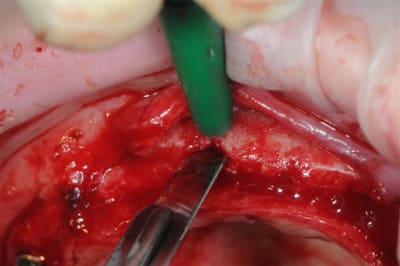

je peux enfin confirmer que la greffe biobank, autorise l'expansion en deuxième intention.

même si je n'ai pas fait un super bombé vestibulaire je me suis permis de faire un mini expansion de crête en particulier sur 22

Pour Posit, l'expansion c'était ma cerise sur le gâteau, et ma façon de prouver que le greffon était parfaitement "vivant" ou au moins travaillable.

l'expansion en 22 à la jonction greffon os propre, faite à l'ostéotome manuel, malgré la non approbation de Thomas, c'est parfaitement passée, et nous avons constatés la parfaite liaison du bloc.

Mon truc c'est l'expansion, sous toutes ses formes,car je pense vraiment qu'il y a encore des progrès à faire.